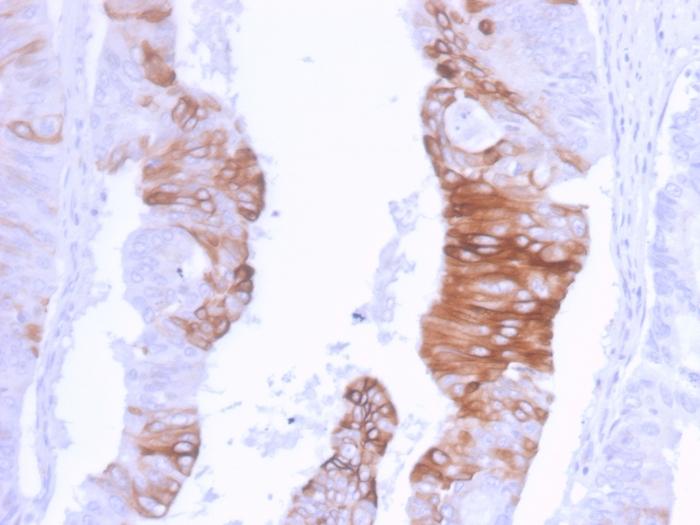

This MAb recognizes an intermediate filament protein of 46 kDa, identified as cytokeratin 20 (KRT20). KRT20 is abundantly expressed in goblet cells and enterocytes of the gastrointestinal tract. It is a useful marker of pancreatic and colorectal cancer. KRT20 is expressed under normal, hyperplastic and neoplastic conditions. It has been detected in adenocarcinomas of the colon, stomachand biliary tract. Breast carcinomas are generally non-reactive. Primary antibodies are available purified, or with a selection of fluorescent CF® Dyes and other labels. CF® Dyes offer exceptional brightness and photostability. Note: Conjugates of blue fluorescent dyes like CF®405S and CF®405M are not recommended for detecting low abundance targets, because blue dyes have lower fluorescence and can give higher non-specific background than other dye colors.

Positive Control

HT29 cell lysate (WB). Human colon carcinoma (IHC).